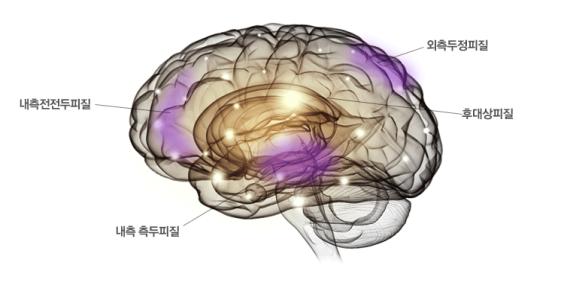

2. 디폴트모드(default mode) 네트워크이다.

디폴트 모드란 컴퓨터가 켜져만 있고 아무 프로그램도 실행하지 않고 있는 상태, 자동차를 시동만 켜고 가지는 않는 상태와 같다.

사람으로 치면 깨어있지만 아무것도 안 하고 있을 때인데, 이럴 때 오히려 활성화되는 뇌 부위를 디폴트모드 네트워크라고 하며 내측 전전두피질, 후대상피질, 내측 측두피질, 외측 두정피질 등이 해당된다.

원래 무언가에 집중해서 실행할 때 디폴트모드 네트워크는 약해지고, 집중하지 않으면 디폴트모드 네트워크는 강해지는 등, 인지조절 네트워크와는 반대로 작동한다.

그런데 ADHD에서는 인지조절 네트워크가 활성화될 때에도 약해지지 않고 과활동을 보이며, 디폴트모드 네트워크 자체의 연결성도 약하다고 한다.